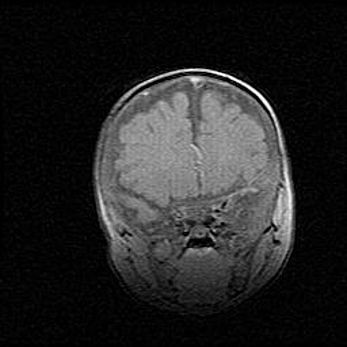

Сообщающаяся гидроцефалия. Кистозная энцефаломаляция головного мозга.

Возраст: 3 месяца 4 дня

Вес: 3100 г

Пол: женский

Окружность головы: 34 см

Срок гестации: 31 неделя

Кистозная энцефаломаляция головного мозга - одна из форм поражения головного мозга в детском возрасте. Характеризуется возникновением множественных и распространённых кист в коре, белом веществе и подкорковых образованиях головного мозга у плодов, новорождённых и детей раннего возраста. Развитие кистозной энцефаломаляции связано с внутриутробной асфиксией и гипотонией, родовой травмой, тромбозом синусов, пороками развития сосудов, инфекциями, сепсисом и другими причинами. Наиболее значимые инфекционные агенты: вирусы простого герпеса, цитомегалии, краснухи, токсоплазмы, энтеробактерии, золотистый стафилококк и другие.